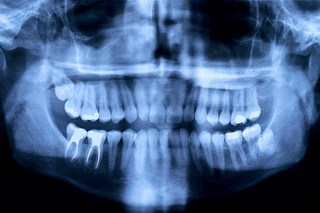

Vi riktar oss främst till vuxna patienter och erbjuder all typ av allmäntandvård såsom undersökningar, lagningar, kronor/broar, tandutdragningar och tandreglering. Vi erbjuder även estetisk tandvård och hjälp att ersätta saknade tänder. Hos oss får du hjälp från första undersökningen till det färdiga behandlingsresultatet, oavsett om du kommer med ett stort eller litet behandlingsbehov.